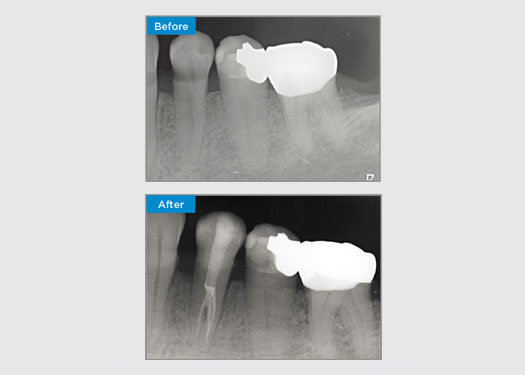

La patiente présentait une pulpite irréversible sur la dent 46. D’après la radiographie préopératoire, la dent 46 présente une racine distale supplémentaire (morphologie de la dent Radix Entromolaris). Une scintigraphie CBCT a confirmé la présence de la racine DL avec une courbure sévère de la racine. Une sélection minutieuse de la lime est essentielle pour cette racine DB délicate.

Dr Jack Lin, endodontiste, Sydney, NSW Australie